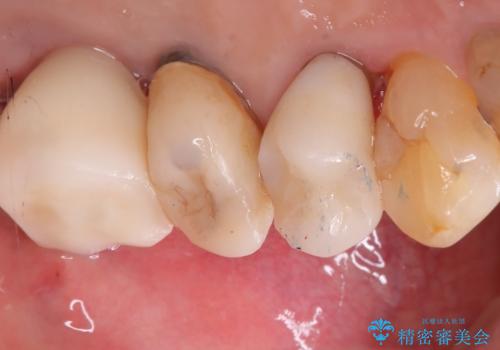

左上6番目の歯が根っこ部分で破折しており、噛むたびに痛みが生じる状態でした。

保存不可能と判断し、抜歯から骨ができるのを3か月待ってインプラント治療を行いました。

歯根破折により抜歯となり、インプラント治療(一回法)にて補綴修復を行いました。

抜歯から3か月程骨ができてくるのを待ってからインプラントを埋入しています。

埋入時には上顎洞粘膜を数ミリ挙上しています。